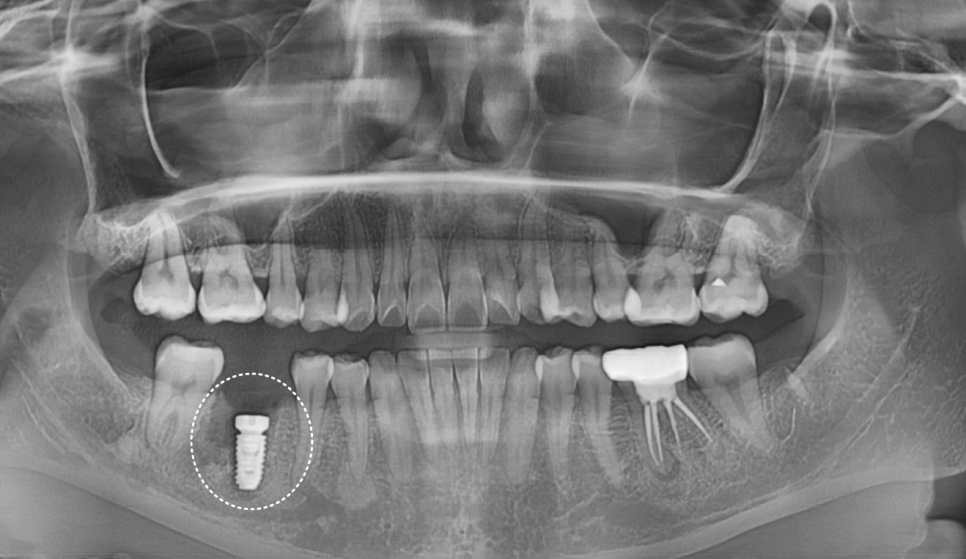

이미 신경치료는 다 되어 있고

사진상에도 치아 뿌리에

염증이 심하게 생긴 상태였어요.

250602 뿌리 끝 염증으로 뼈가 녹은 상태

CT를 찍어보니 뼈 소실이 생각보다 많이 진행되어 있었습니다.

당일 발치 후 바로 뼈이식과 함께 임플란트를 심었습니다.

이렇게 즉시 식립하면 뼈 손실을 최소화할 수 있거든요.

250715

정확한 각도와 위치에 심어졌습니다.

2달 후 다시 내원하셨을 때

뼈에 임플란트가 잘 붙었는지 확인해 봤어요.

전 : 250602 / 후 : 250725